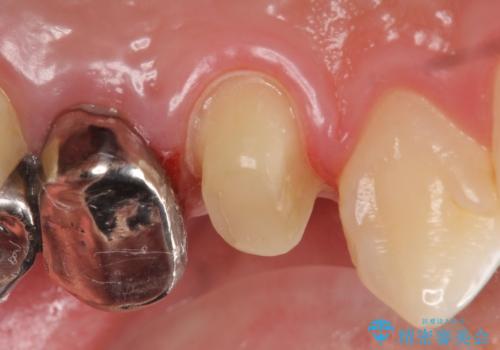

診査の結果、左上4番目の歯の神経が死んでおり、根尖に膿が溜まっていることが原因とわかりました。

そのため左上4番目の歯は根管治療を行い、歯茎の膿の出口の消失を確認後、オールセラミッククラウンによる補綴を行いました。

今回用いたオールセラミッククラウンはジルコニアフレームという白い素材の上にセラミックを盛っているため、審美性が非常に高いのが特徴です。